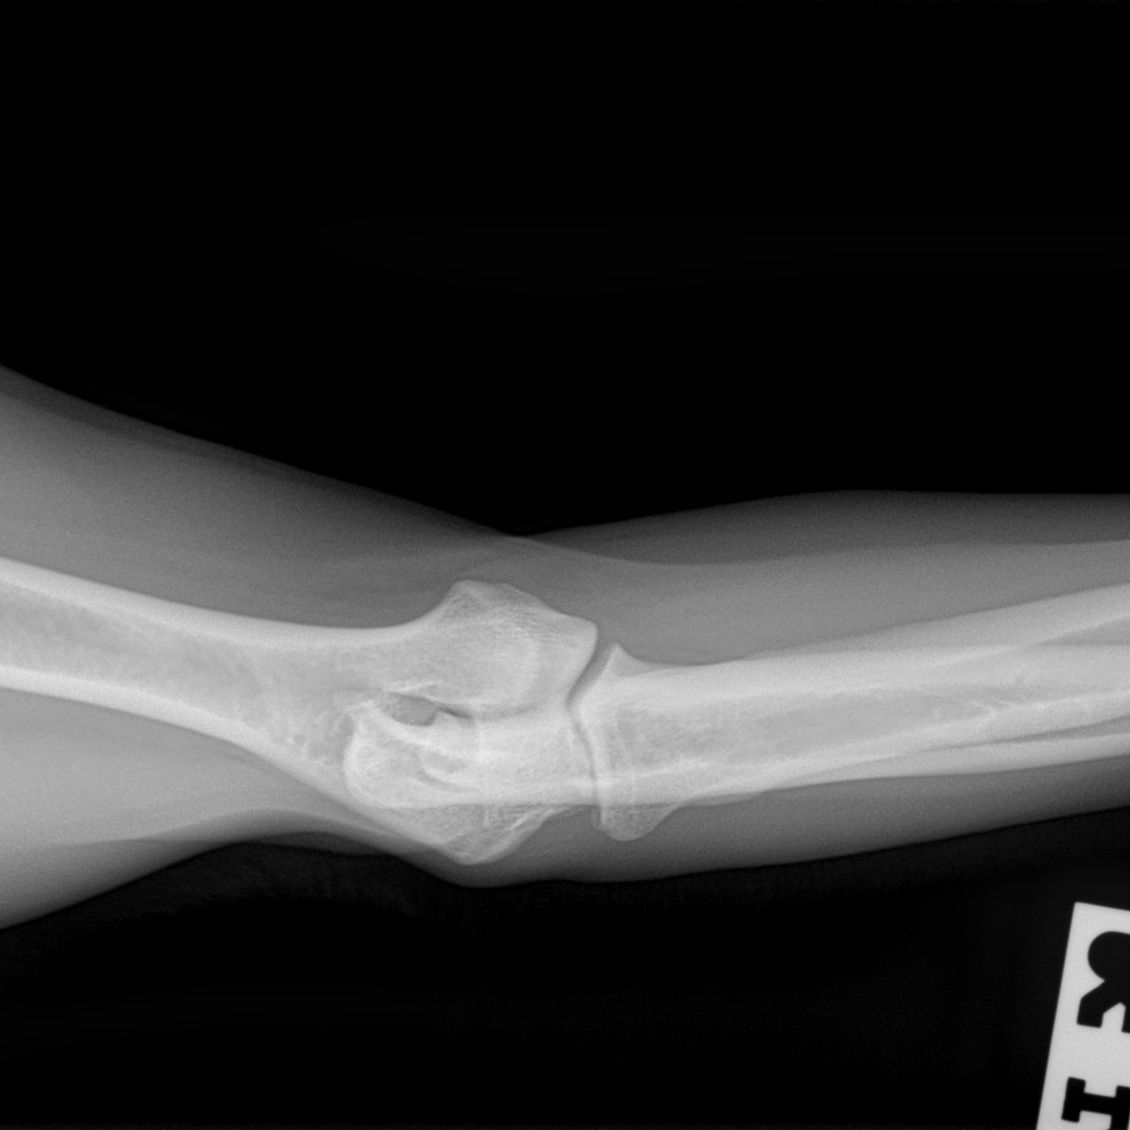

Hieronder foto's van Guus genomen met onze nieuwe DRgem rontgen. Beoordeeld met de hoogste score door de Raad van Beheer op Kynologisch gebied

Elleboogdysplasie (ED) onderzoek

Elleboogdysplasie is een ontwikkelingsstoornis van de ellebooggewrichten, met name het kraakbeen is aangetast. Deze aandoening kan erfelijk zijn, maar omgevingsfactoren spelen soms ook een rol. Er zijn honden die op jonge leeftijd al problemen ondervinden door ED, soms komt het pas op latere leeftijd tot uiting. Om te kunnen zien of uw hond ED heeft zijn röntgenfoto’s van de ellebogen nodig.

Voor alle andere rassen volstaat een onderzoek met twee foto’s per elleboog. Meestal passen wij een lichte sedatie toe bij het maken van de officiële ED-foto’s. Dit is nodig om een kwalitatief goede foto te maken, welke aan de hoge eisen van de beoordelingscommissie moet voldoen. Uw hond moet op zijn of haar zijde en borst liggen, waarbij de elleboog in verschillende houdingen wordt gelegd.